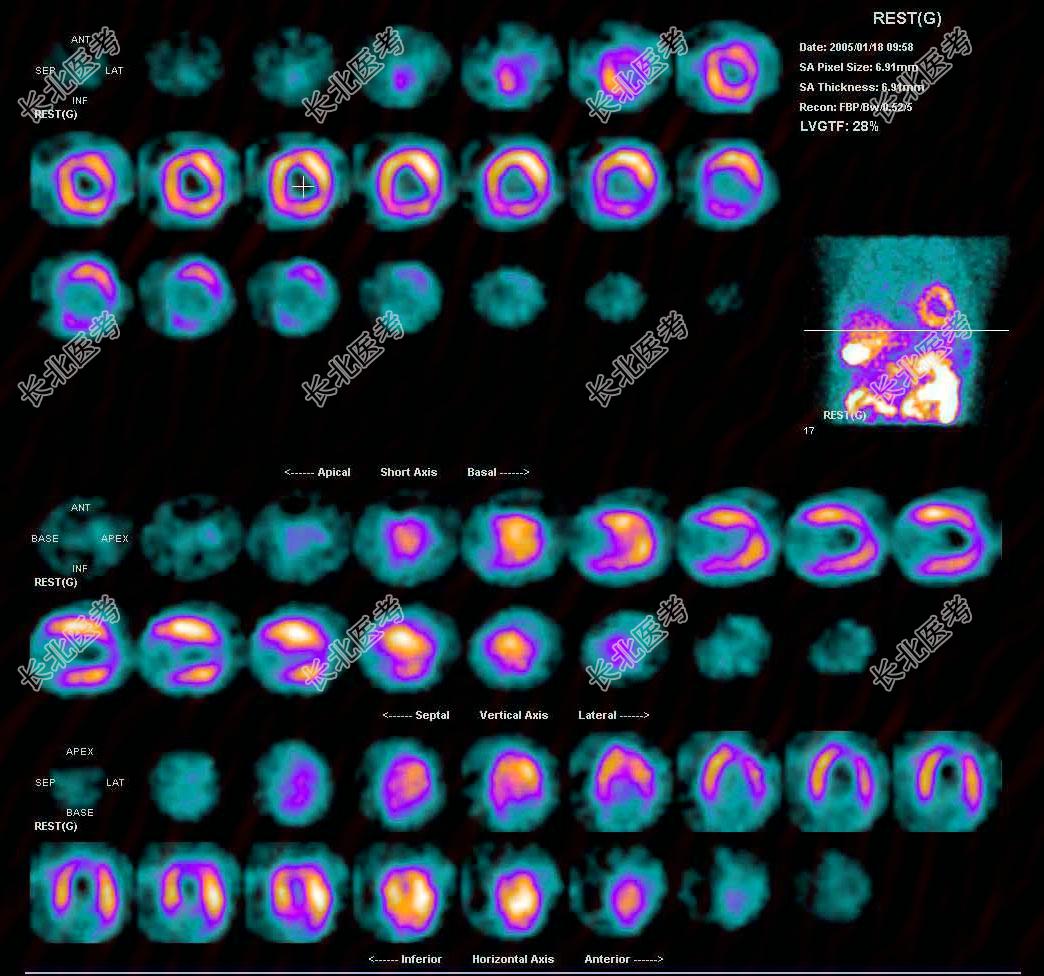

- 多项选择题男性,53岁, 反复胸闷10年。查体:心界扩大。行

Tc

-MIBI静息心肌灌注显像如图, 可能的诊断是 ( )

A、左心室心尖、部分前壁、侧壁缺血

B、扩张型心肌病

C、缺血型心肌病

D、肥厚型心肌病

E、大致正常的影像